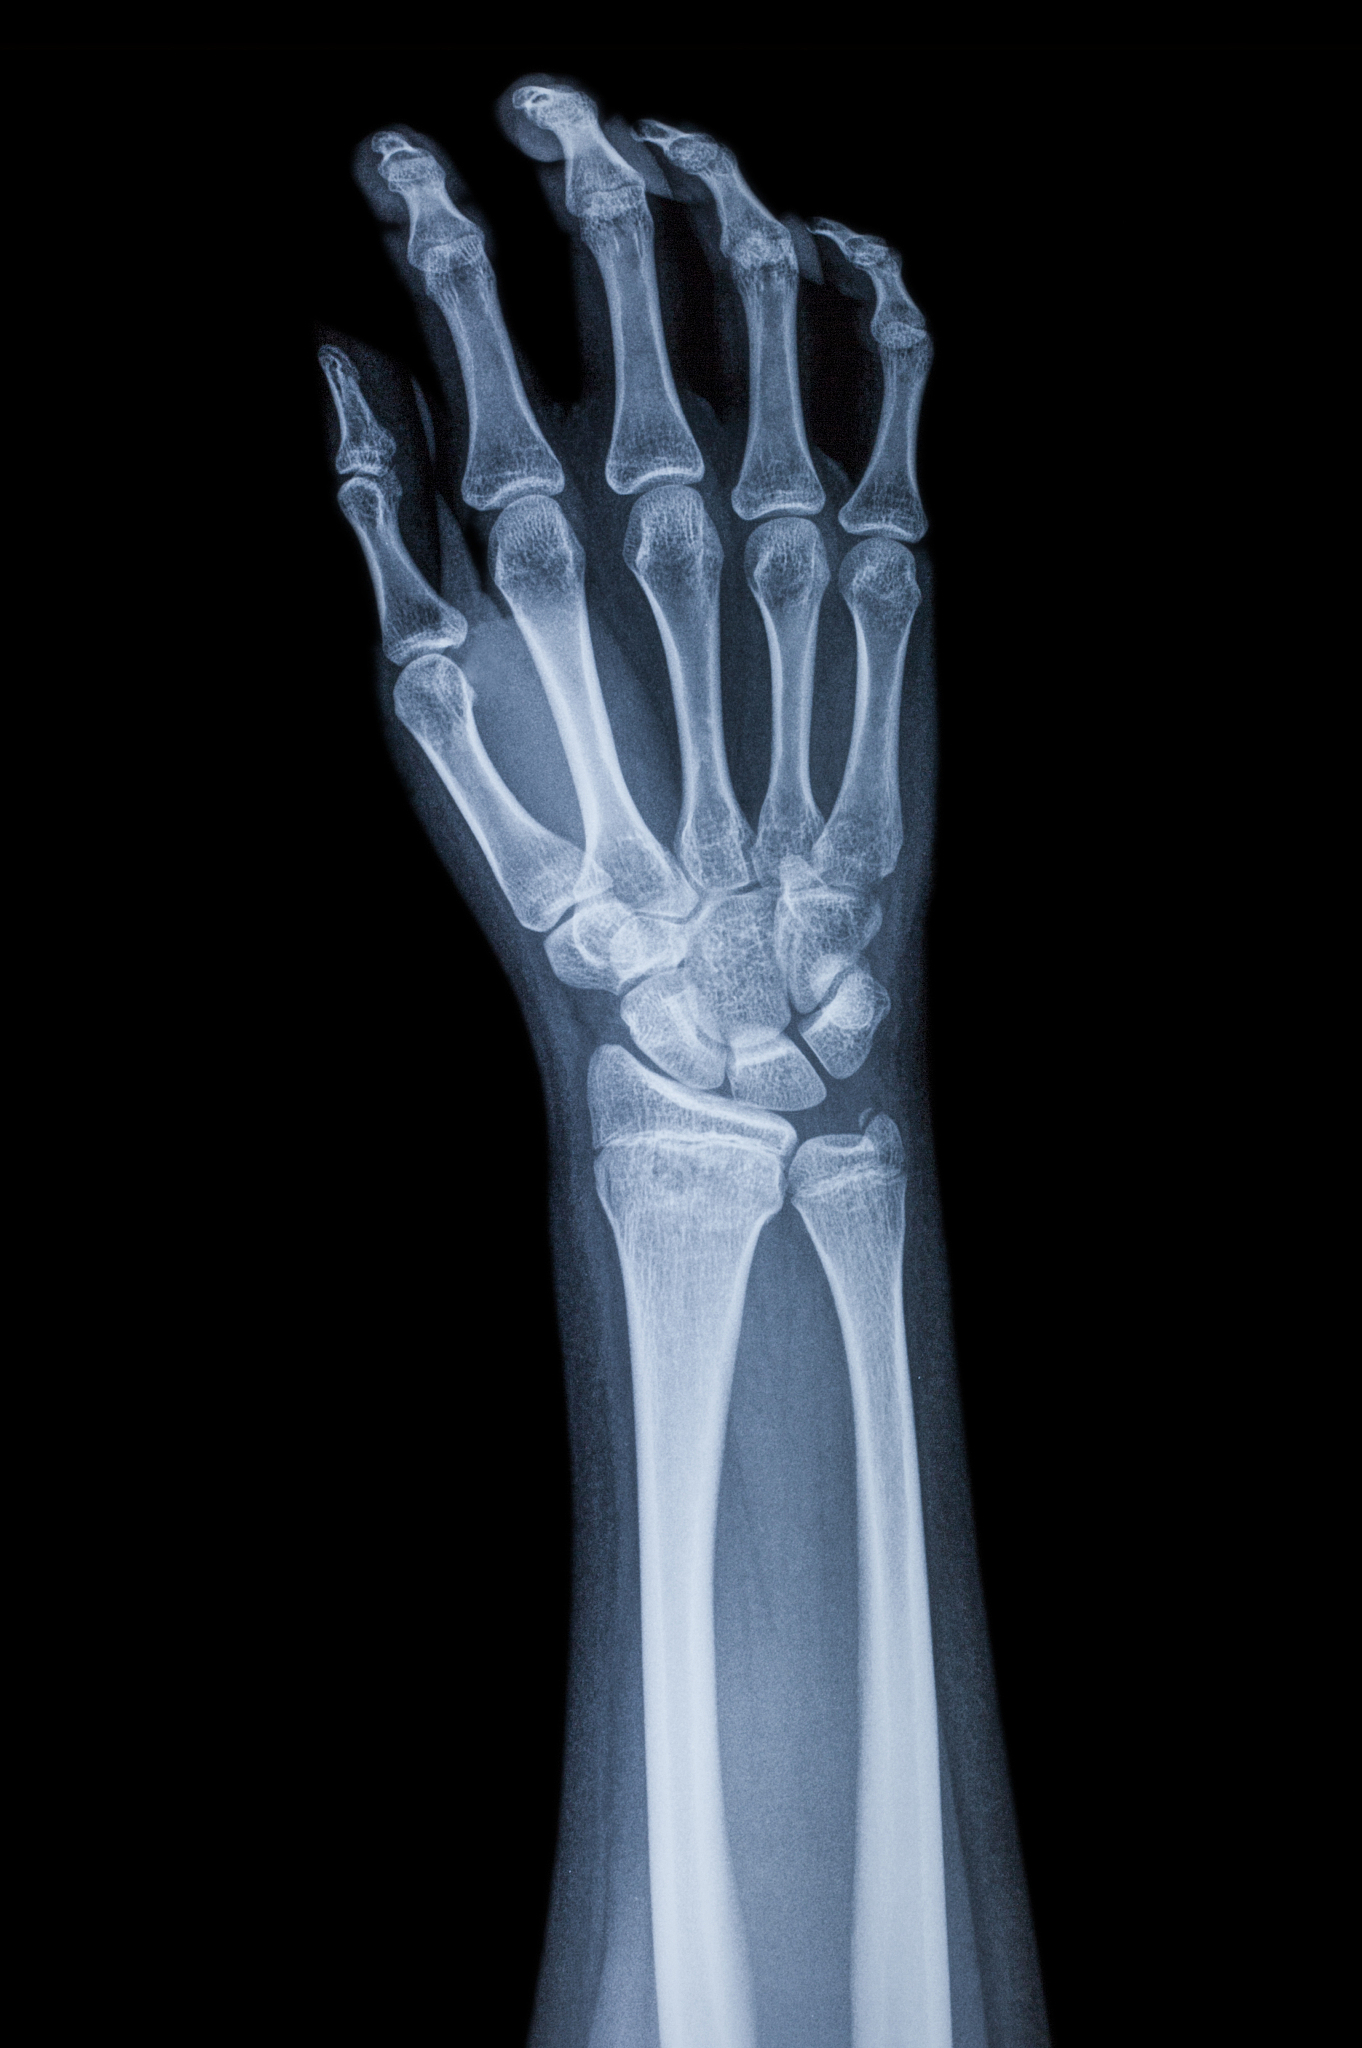

手部骨折是指手部骨骼的断裂或破裂。手部骨折可能涉及手掌骨骼、腕骨、指骨或掌骨。常见的手部骨折包括腕部骨折、掌骨骨折、指骨骨折等。

手部骨折的常见症状包括剧烈疼痛、肿胀、淤血、活动受限、畸形或变形等。如果怀疑手部骨折,应立即就医进行确诊和治疗。

手部骨折:症状、治疗和康复